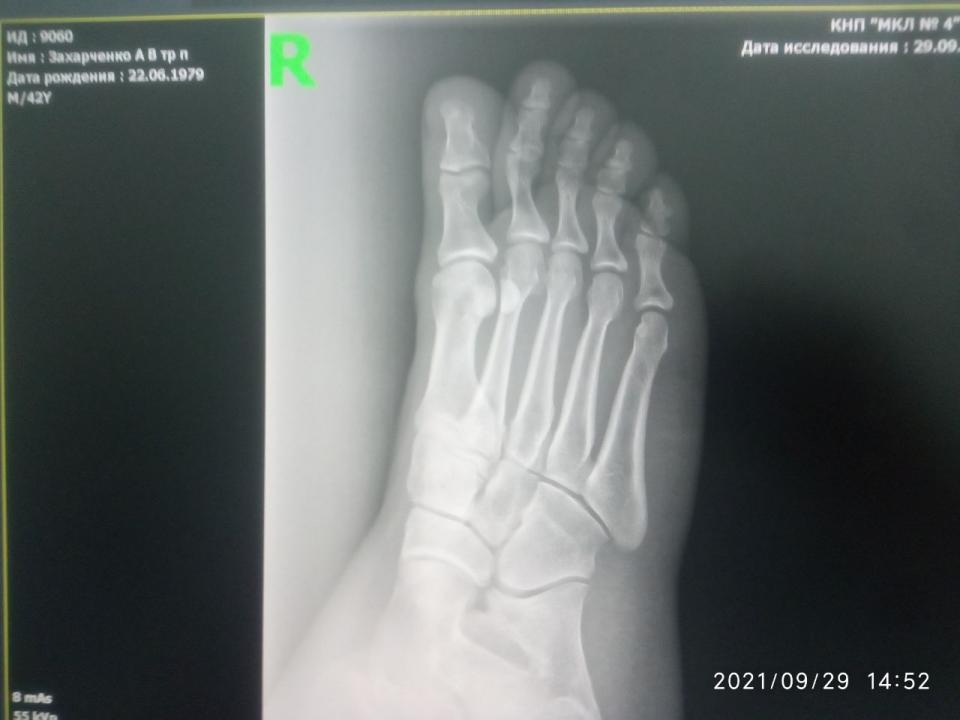

andreyyy Опубликовано 5 октября, 2021 Опубликовано 5 октября, 2021 Драсьте На фоне истощения организма, плохо заживающих ранок, падения иммунитета, что является вообще отдельной темой, не для обсуждения, я неудачно спрыгнул с брусьев. С невысоких. С собственным весом около 70 кг. Просто знаете, бывает, что не достаточно самортизировал и в стопе возникла боль при приземлении. Это было, дай бох памяти, в понедельник прошлой недели. Т.е. 8 дней назад. Сначала боль была несильная. На утро легкая, вполне себе не вызывающая беспокойства. Пошел на работу. От проходной до моего участка работы пешком далеко. Т.е. каждодневный поход н аработу - это всегда большая нагрузка в плане ходьбы. Особенно если опаздываю и иду быстрым шагом. Так я сильно мучился, когдда несколько месяцев не заживали мозоли-волдыри, нратертые обувью. Я купил эластичный бинт и перемотал стопу. По неопытности перетянул сильней необходимого. Идти стало еще больней. Шел через боль, пока боль не стала очень сильной. Остановился, размотался... К вечеру нога разболелась очень сильно. Когда говорю очень, то это буквально. Обезболился, лег спать. Проснулся утром, а боль уже невыносимая. Невозможно ступить на ногу вообще. Больно даже легонько прикоснуться пальцем к коже стопы. Я уссыкаюсь, а не могу идти. Я зову на помощь, мне несут ведро. При этом еще и морозить стало. Я измерил - 39. Напился Парацетамола, Ибупрофена, уколол 3 кубика кетанова и несколько ампул налбуфина. К последнему толерантность и он плохо действует в плане обезболивания. Зависимости нет (была), но толерантность высокая. Одна ампула вообще не дает эффекта. Как-то так. В общем, обезболился и на работу не пошел. Интенсивность боли показалась ненормальной и я поехал на такси в травмпункт. А, сначала получил направлениеп от семейной. Уже попускали лекарства, даже покачивания в такси вызывали сильную пульсирующую боль. Наступил на камушек, так заорал криком... Травмпункт отказался принимать, т.к. они работают только в первые сутки после травмы. Моя семейная такая - всю жизнь меня куда-то направляет, где говорят, что она дура и этот не к ним. Умеет только бубнеть, как сложно ей живется после реформы и как сбоит программа (просто время отклика на клик было чуть дольше чем на хорошем современном ПК, все работает четко, но она бубнит, что вот снова невозможно работать, реформа....). Короче, я там начал ругаться. Я еще нервный последнее время и на транках, которые не работают уже нихера. А шишки потерял ( Добился приема заведующего отделением. Направил на рентген. Я сфотографировал снимки на мониторе и показал ему на телефоне. Он сказал, что все пучком, все в целостности. Прописал покой, холодные компрессы, легкая намотка и капустный лист. Не шутка. А если будет болеть, немид. Если вдруг понадобится больничный, то к семейному. Вот эти "если" умиляли. Я ему же объяснил, что я несколько часов назад не мог до туалета дойти. На следующее утро та же история. В течение дня я всем чем можно обезболиваюсь, соблюдаю режим щадящий, но стоит заснуть и проснуться, как боль невыносимая и невозможно вообще даже с палочкой пройти и пару шагов. Я обнаружил, тчо кетанов не работает совсем. Вчера поставил 3 кетанова и 3 трамадола и боль ушла примерно на 60% Трамадол был последний. Оставалось на всякий случай в заначке 3 кубика. Сегодня ночью я жменями жрал пенталгин, темпалгин, ибупрофен, т.к. не хотел будить никого. Утром докупили кетанов. 2 кубика. Полнейшее отстутствие эффекта. Еще 2. Вообще ноль При этом я абсолютно уверен, что кетанов на мне работает отлично. От сильной зубной или послеоперационной боли 2 кубика снимают боль полностью. Не на долно, но полностью. Никак не связан его эффект с падением эффективности опиоидов. Я озадачен. Я не могу придумать, по какой еще причине он может не работать кроме проблем с кровообращением. С кровообращением, кстати, и правда жопа. Кончики пальцев на ногах потеряли чувтствительность. Но нога-то распухшая, кроме как кончики пальцев всюду чувствительнсоть есть. Уколол 1 налбуфин. Сижу терплаю. Дергает и пульсирует. Усомнившись в правильном ракурсе снимка, я повторно через семейного выбил направление к нашему местному травматологу. Там сделали снимог на пленку. Не знаю, как его выложить. Не могу сфотографировать, чтобы что-то было четко видно. ВЫстоял очередь к травматологу... И хорошо, что с криком "Да пошел ты " выскочил, хлопнув дверью, что штукатурка посыпалась, ибо так психанул, что если бы не выскочил, то перее..л бы его палкой (я с папиной палкой сейчас хожу), Он отказался даже смотреть снимки. К нему только по записи. По направлению нельзя. К тому же он последний день перед отпуском. Последнее он повторил несколько раз. К чему? Сейчас-то он на работе! Я стою с сильной болью, приехал на такси на одолженные деньги, а он давит лыбу и говорит, что он уже почти в отпуске и меня не примит. Ну я начал колоть диклофенак, пить Серротопептидазу. Никаких изменений. Первый рентген (цифровой) Показать Показать Показать Показать Показать Селфи Показать Селфи только что Показать Диагноз поставли "или растяжение или надрыв". Прошу совета. Я сейчас и так очень сильно погружен в решение своих других проблем и не могу много времени выделить на походы по больницам. Ждать и само заживет или что-то идет не так ? КАкие варианты ? Навскидку устрпоит. Вообще чтоб понимать, что МОЖЕТ быть. Чем обезболиваться ? Я не могу вспомнить хороший нецентрального действия преп, который тоже хорошо помогает в плане обезболивания (чуть ли не на уровне кетаролака). Что из сильного ненаркотического ? буду пробовать все.